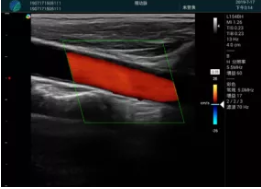

頸動(dòng)脈血流充盈飽滿,無外溢

肝內(nèi)血管顯示清晰,血流敏感無外溢